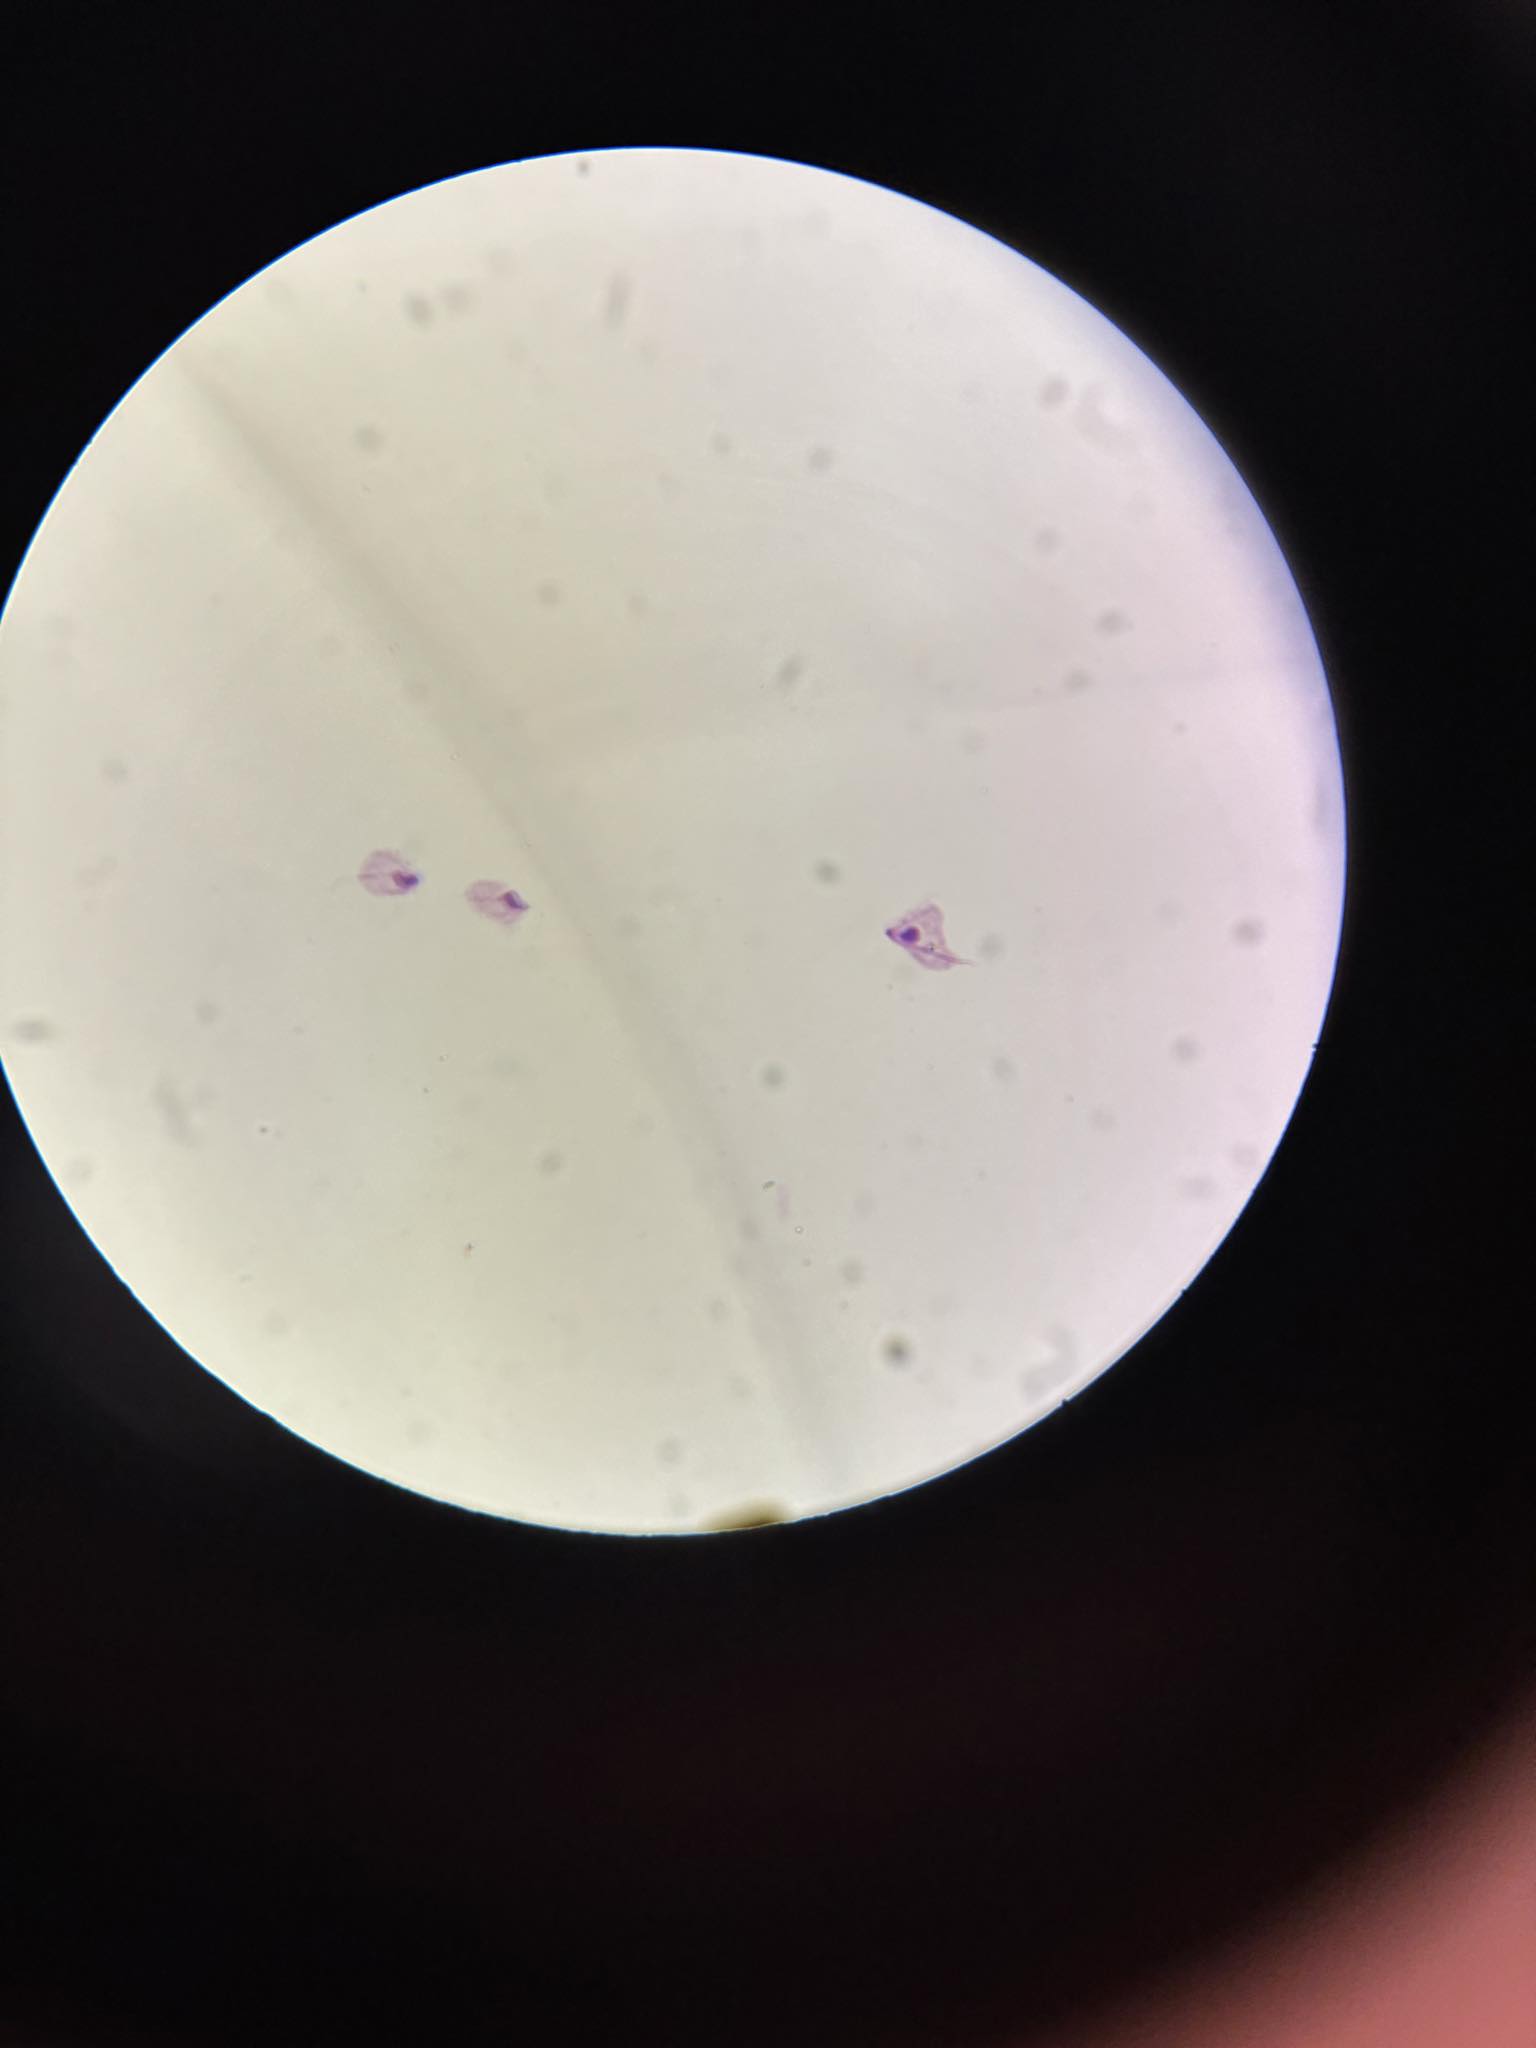

plasmodium falciparum stadia schizogonii krwinkowej

plasmodium falciparum stadia schizogonii krwinkowej